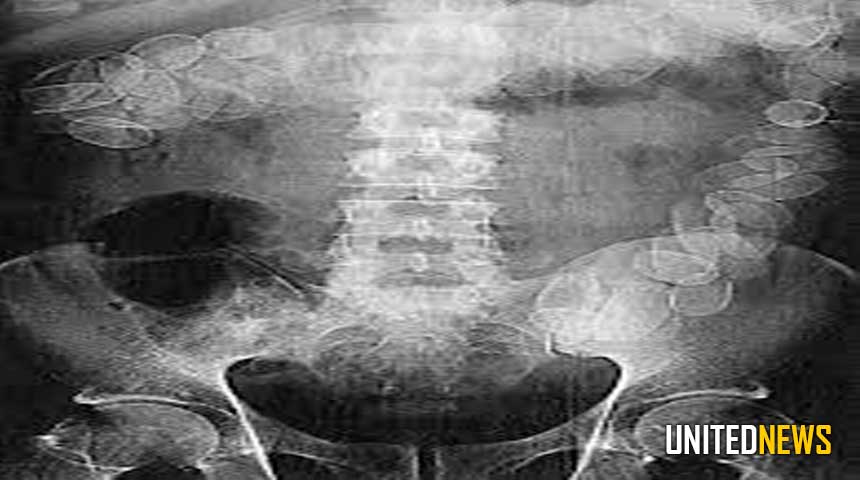

Foto: Een Röntgen foto van een cocaïnesmokkelaar met bolletjes op zijn maag.